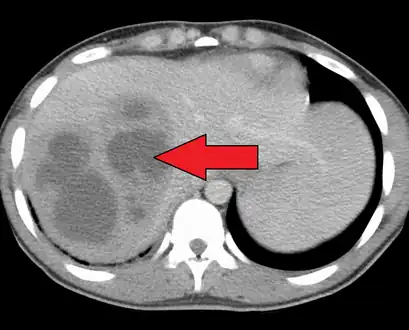

| A large pyogenic liver abscess presumed to be the result of appendicitis | |

a)Day 1 showing pyogenic liver abscess b)hospital day 21 showing improved pyogenic liver abscess, after intravenous antibiotic